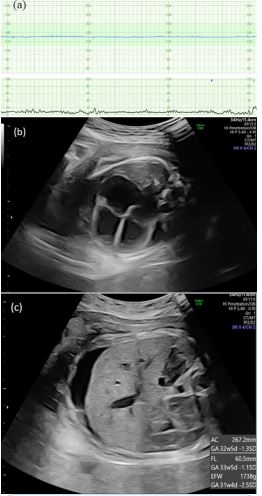

The mother was a 29-year-old primigravida with no history of transfusion, past illness, or relevant family condition. Screening at 12 weeks of gestation revealed the presence of anti-M antibodies; however, as they were reactive only at low temperatures, their clinical significance was considered minimal, and standard management was continued. At 26 weeks, the estimated fetal weight was 764 g (−1.6 Standard Deviation (SD)), suggesting fetal growth restriction; growth thereafter remained between −1.6 SD and −1.8 SD. At 29 weeks, placenta previa was diagnosed, and a cesarean section was scheduled at 36 weeks. At 35 weeks and 5 days, fetal heart rate monitoring showed absent baseline variability (Figure 1a), and ultrasound revealed fetal cardiomegaly, pleural effusion, and ascites (Figure 1b-c). Emergency cesarean section was performed for non-reassuring fetal status and placenta previa.

Figure 1: Cardiotocography and fetal ultrasound at 35 weeks and 5 days of gestation. (A) Fetal heart rate showed absent baseline variability. (B) Ultrasound revealed a cardiothoracic area ratio of 40.4%, indicating fetal cardiomegaly, and (C) Pleural effusion and ascites.